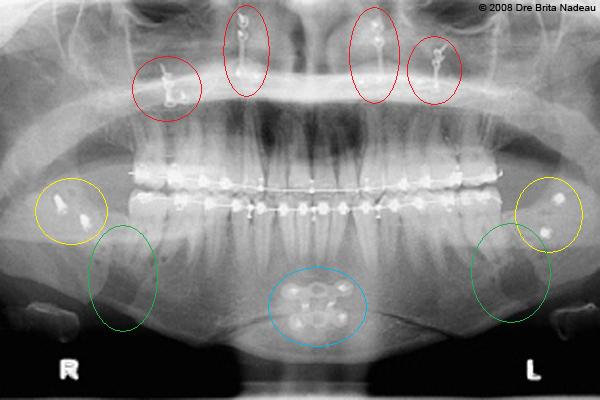

- 13 DÉCEMBRE 2007 - L'extraction de mes dents de sagesse

- Photos & radiographies